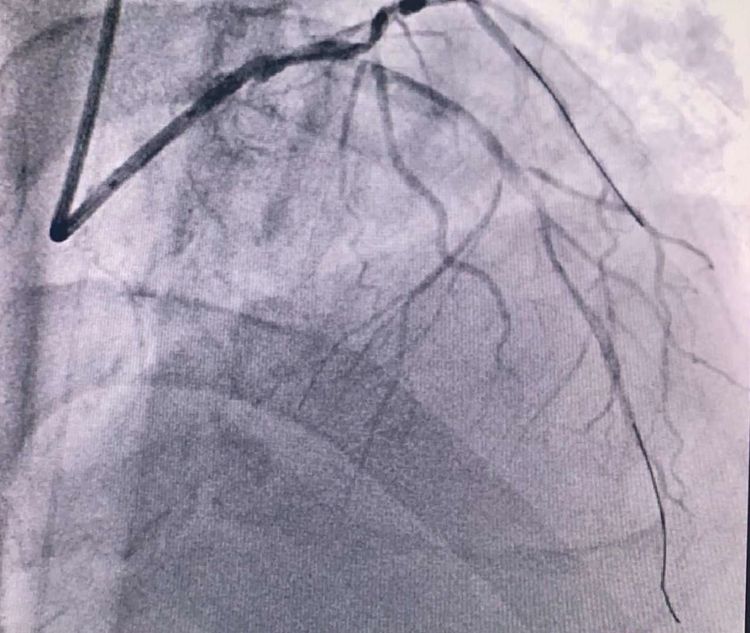

患者前降支、右冠100%閉塞,LCX中段60%狹窄。命懸一線,手術(shù)臺(tái)上持續(xù)胸痛。和患者家屬及時(shí)溝通后,決定行PTCA術(shù)。血壓低至60/40mmHg,在主動(dòng)脈內(nèi)球囊反博的支持下緊急行PCI術(shù)。軌道很快建立,導(dǎo)絲也及時(shí)通過病變血管,噩夢來了,患者發(fā)生室顫了。在吳棟梁院長的指揮下,李陽主任和心臟團(tuán)隊(duì)的成員共同努力下,除顫、冠脈內(nèi)溶栓、多個(gè)球囊輪流上陣,患者病情平穩(wěn)了,罪犯血管及時(shí)開通,血流恢復(fù)三級(jí)血流。平安下臺(tái),準(zhǔn)備擇日再處理冠脈情況。